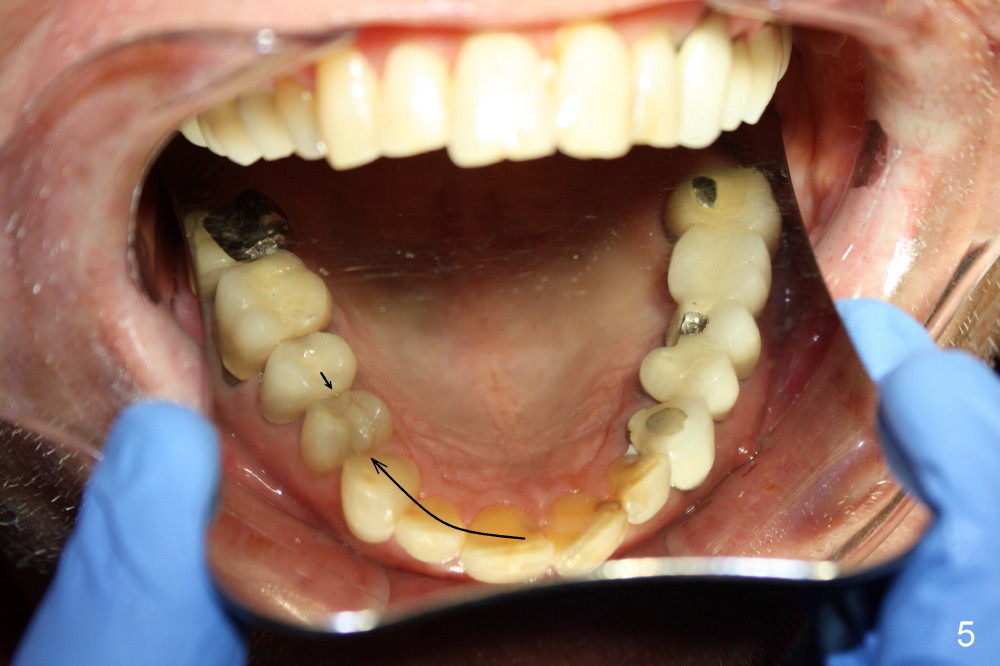

Although there is apical infection associated with the upper left first bicuspid (Fig.3 *), orthodontic treatment consists of extraction of a single tooth: the upper right first bicuspid (Fig.4,5: x), minor movement of the posterior teeth (Fig.4,5 smaller arrow) and major movement of the anterior teeth (bigger arrow). Fig.6 shows simulated tooth movement.